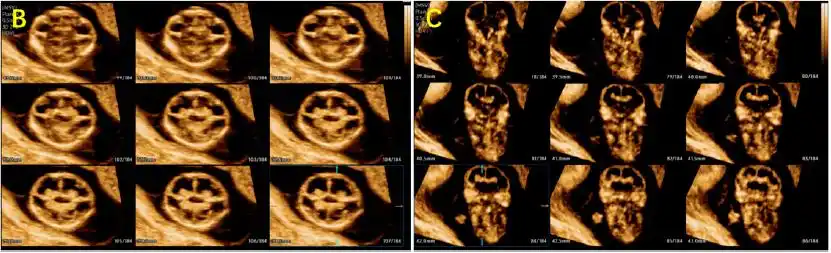

【病例分享】 图解联体胎儿_超声_bal_singh